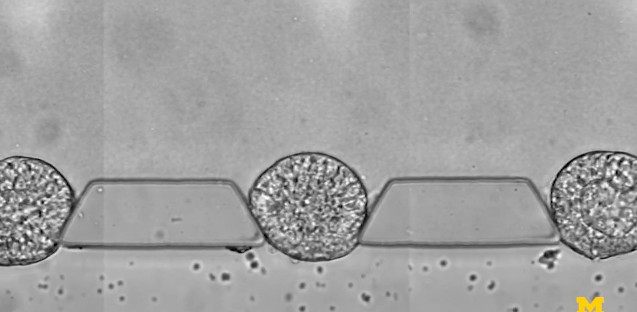

研究人員由此開發(fā)出來一種微流體裝置——由三個通道組成,分別用于放置細(xì)胞可嵌入的材料,裝載干細(xì)胞,以及輸運(yùn)刺激干細(xì)胞分化的因子,借此研究人員能夠控制干細(xì)胞在早期人類胚胎中面向主要細(xì)胞譜系的分化,可以可靠地產(chǎn)生數(shù)百或數(shù)千種類似胚胎的結(jié)構(gòu)。

圖 | 微流控芯片的特寫照片,該芯片幫助干細(xì)胞組織成胚胎樣結(jié)構(gòu),用于研究早期人類發(fā)育(來源:Fu Lab, Michigan Engineering)

為了模擬胚胎著床后的發(fā)育階段,即羊膜囊開始形成的時候,也是干細(xì)胞向分化成組織邁出第一步的時候,研究小組在一個可伸縮的三通道微流體系統(tǒng)中嘗試培育干細(xì)胞。中央通道包含一種模擬子宮壁的凝膠,兩側(cè)有一個通道用于為干細(xì)胞補(bǔ)充營養(yǎng),另一個通道用于遞送引導(dǎo)。